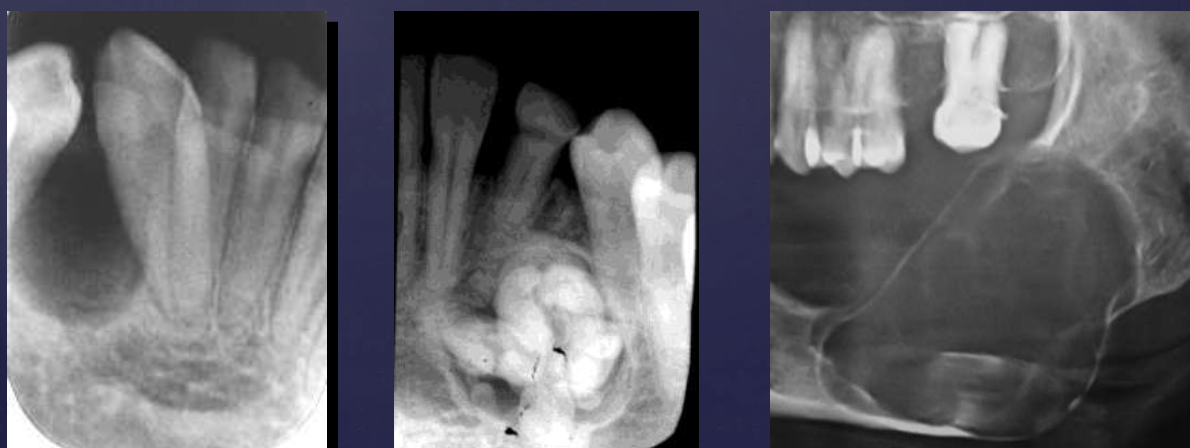

radiographic features of adenomatoid odontogenic tumors

associated w/ unerupted tooth (commonly max lateral incisor)

mixed radiodensity: mostly radiolucent w/ some radiopacity within

displacement of adjacent teeth

radiographic features of calcifying epithelial odontogenic (Pindborg) tumors

mixed density- central radiolucency with radiopaque foci

maybe associated w/ unerupted tooth

expansile- expands cortex

root resorption possible

T/F: you can see B/L expansion in this radiograph

false, since this PAN is a superimposed image- you cannot tell